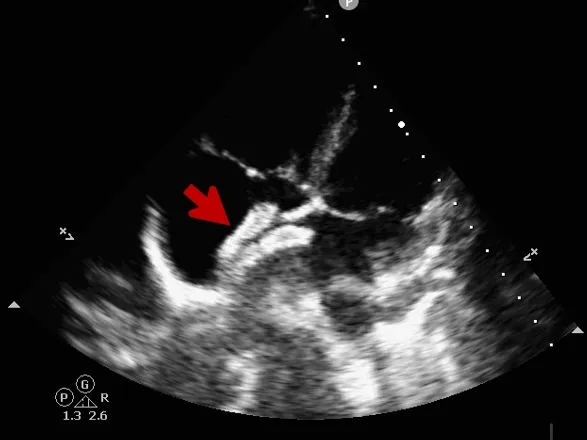

封堵器释放

撤出钢缆释放封堵器

超声下可见封堵器形态良好,封堵成功

释放后评估

封堵器位置正确、形态良好

彩色多普勒血流成像显示无残余分流存在

封堵成功